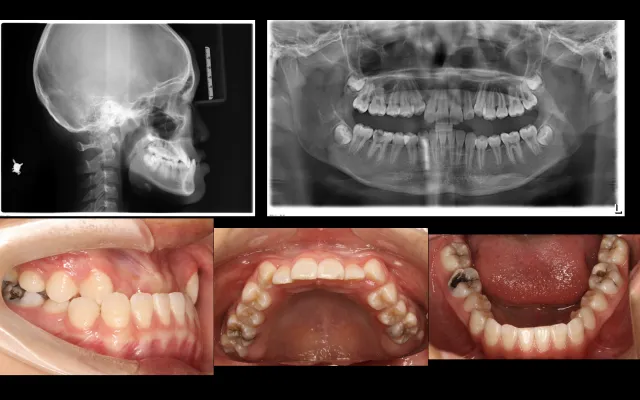

反颌病例的矫治策略(升级版)

1.反颌形成原因

2.不同时期反颌的治疗理念及治疗方法

3.如何高效解决反颌

4. 10个典型反颌案例分析

5.牙性反颌、功能性反颌、骨性反颌的诊断及鉴别诊断

6.牙性反颌功能性反颌的矫治策略及解析

课程重点:

骨性反颌的矫治策略、骨性反颌➕开颌的矫治策略、

骨性反颌➕中重度拥挤的矫治策略、

骨性反颌正畸掩饰治疗的托槽转矩选择、

骨性反颌的拔牙病例解析